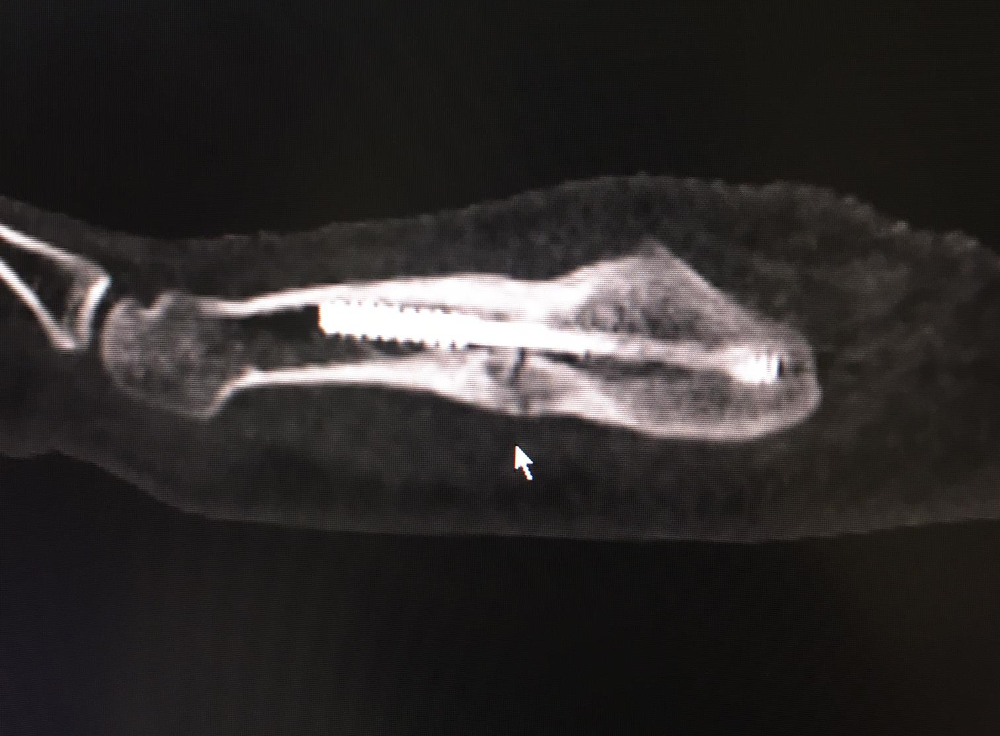

Die Bruchstelle ist im Röntgenbild gut ersichtlich

Acht Wochen dauert die Pause, dann steige ich wieder ins Training ein. Nach der ersten Einheit bei Wacker Thun verspüre ich zwar Schmerzen im Fuss, reise ein paar Tage später dennoch an den Zusammenzug des Nationalteams in der Hoffnung, dass es dann schon geht. Dass die Schmerzen dann anhalten, schiebe ich auf die erhöhte Belastung und will einfach einige Tage mit dem Teamtraining aussetzen. Als sich ein Kollege im Nationalteam den Fuss vertritt, fahre ich ihn zum Arzt und lasse mich dann auch in den Tomografen schieben. Ich will Klarheit. «Sch…, jetzt wird es eng mit der EM», schiesst mir durch den Kopf, als mir der Arzt mitteilt, der Fuss sei wieder gebrochen. Eine erneute Operation kommt nicht in Frage, dann wäre die EM-Teilnahme futsch.